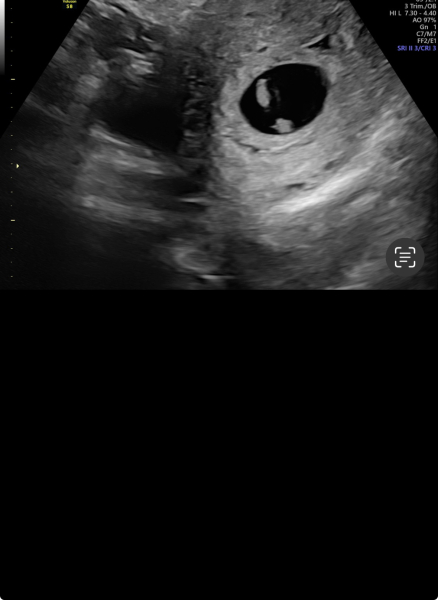

7 week scan

Anyone know if there’s a chance there could be twins?